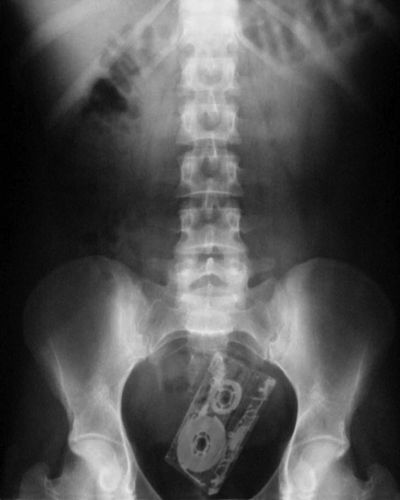

Os objetos mais BIZARROS encontrados no ânus pelos médicos

Fita Cassete